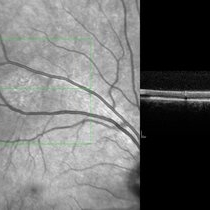

Unilateral Acute Idiopathic Maculopathy

Image on right shows infrared photo of the lesion of interest. SDOCT (image on left) through the lesion of interest shows hyperreflectivity of the RPE with disruption/loss of detail of the IS/OS junction.

Photographer: Kidron Robertson - Georgia Eye Institute of the Southeast

Imaging device: Heidelberg Spectralis

Condition/keywords: chorioretinal inflammations, Coxsackie, unilateral acute idiopathic maculopathy